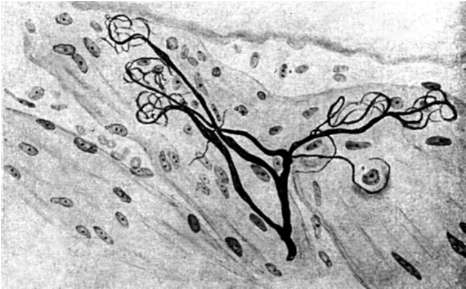

Периодонт представлен главным образом пучками коллагеновых волокон, состоящих из коллагена 1-го типа, которые лежат в периодонтальной щели (между цементом корня и компактной пластинкой альвеолы). Кроме них, присутствует незначительное количество тонких ретикулиновых и незрелых эластических - окситалановых волокон, обычно рыхло расположенных около сосудов. Одним концом коллагеновые волокна прикреплены к цементу корня зуба (рис. 4-3), другим - к костной ткани альвеолы.

Рис. 4-3. Коллагеновые волокна, проникающие в вещество цемента (Гемонов В.В.)